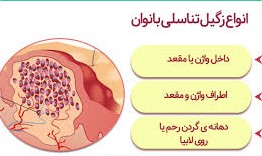

زگیل تناسلی در زنان: علائم، علت، درمان و پیشگیری

یکی از شایع ترین بیماری های جنسی و مقاربتی زگیل تناسلی می باشد که ناشی از ویروس اچ پی وی یا پاپیلومای انسانی (HPV) ایجاد می شود. آلوده شدن به گروهی از ویروس های اچ پی وی در زنان میتواند منجر به سرطان رحم و سرطان دهانه رحم شود. برخی دیگر از انواع ویروس اچ پی وی میتواند باعث ابتلا به سرطان روده بزرگ شوند. عفونت HPV ویروسی به شدت مسری است که از شایع ترین بیماری های جنسی به شمار می رود. زگیل تناسلی در زنان بسیار خطرناک تر از مردان می باشد.

- زگیل تناسلی می تواند در هر بخشی از بدن که در معرض تماس جنسی قرار می گیرد، ایجاد شود به طور مثال، زگیل در زنان در نواحی مانند واژن، دهانه رحم یا کشاله ران، دهان، گلو و … (در مردان، آلت تناسلی، اسکروتوم، ران یا کشاله ران) ظاهر می شود.

بیش از 100 نوع از ویروس پاپیلومای انسانی (HPV) می توانند انسان ها را آلوده کنند و از این تعداد، بیش از 40 نوع از آنها دستگاه تناسلی و مقعد مردان و زنان را آلوده می کنند. گاهی اوقات ضایعات تناسلی به نام زگیل های وریدی ایجاد می شوند. همچنین زیر گروهی از HPV ها می توانند به تغییرات پیش سرطانی در رحم و سرطان گردن رحم منجر شوند.